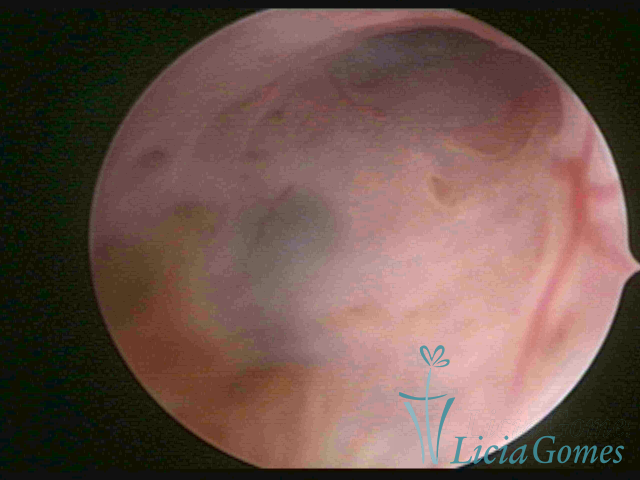

ADENOMYOSIS

The presence of endometrial tissue on the muscular layer of the uterus.

Video hysteroscopy allows diagnosing the lesions next to the superficial myometrial layers next to the endometrium, allowing the view of in situ, purplish, or chocolate brown lesions.